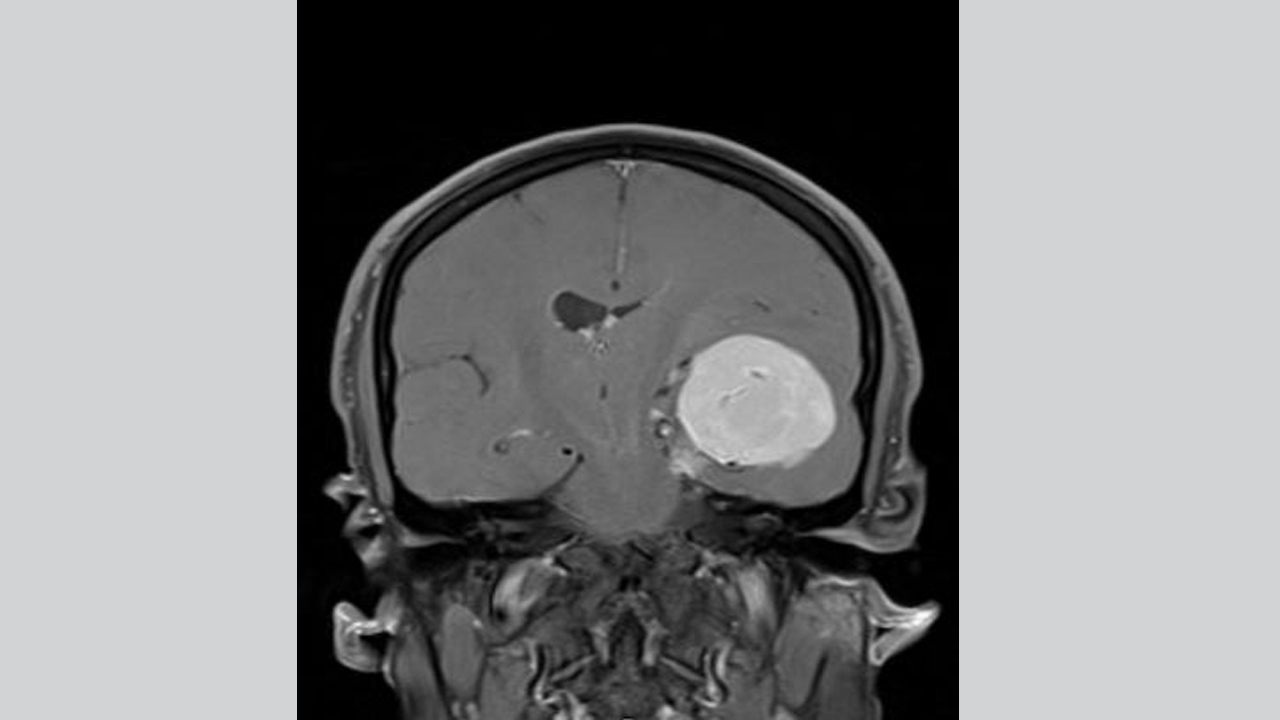

وبعد عشر سنوات من البحث والقلق نتيجة عدم الحصول على تشخيص للحالة، قرر مهند حجز موعد لإجراء تصوير بالرنين المغناطيسي، فبينت النتائج وجود ورم دماغي بحجم كرة البليارد في الجانب الأيسر من الجمجمة وكان ذلك يضغط على الدماغ، وعندها لجأ إلى مستشفى "كليفلاند كلينك أبوظبي"، حيث قرر الأطباء استئصال الورم.

واستغرقت عملية الاستئصال ثماني ساعات، وكانت معقدة جداً بسبب موقع الورم الكائن في قاعدة الجمجمة وضغطه على الدماغ ووجود شبكة من الأوعية الدموية فيه، لذلك استخدم الأطباء تقنية متطورة تُدعى "الملاحة العصبية"، التي تقوم بعملية مسح تفصيلية ثلاثية الأبعاد للدماغ للمساعدة في توجيه العمل الجراحي وضمان إمكانية إزالة الورم دون الإضرار بأي من أنسجه السليمة المحيطة، وبالفعل خضع المريض للجراحة وتمكن بعدها من التعافي والعودة إلى حياته العائلية والمهنية.

قال أخصائي الجراحة العصبية في مستشفى "كليفلاند كلينك أبوظبي، الدكتور محمد سامي الحمادي، ": "كان الورم في دماغ مهند من أكبر الأورام التي رأيتها لدى المرضى هنا في أبوظبي، فقد نما على مدى فترة طويلة، ما أتاح تشكّل شبكة أوعية خاصة به وتسبب بحدوث انتفاخ كبير أدى إلى دفع الدماغ لأكثر من سنتيمتراً عن المركز. كان لا بد من استئصال الورم، وإلا لكان استمر بالنمو وأدى إلى تفاقم الأعراض".